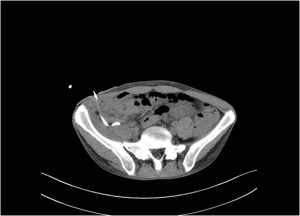

Comentario: en este paciente se inició la colocación del drenaje guiandolo por eco ya que es la primera elección (no radiación y misma accesibilidad), pero el paciente a pesar de la anestesia local presentaba mucho dolor y terminó moviendose durante la intervención, sacando el drenaje de la colección. Ante este contratiempo se decidió guiarlo por TC. A continuación, muestro imágenes de la intervención guiado por eco y por TC. Pero debe quedar claro que la primera opción para guiar el drenaje es la eco debido a que es menos perjudicial para el paciente.